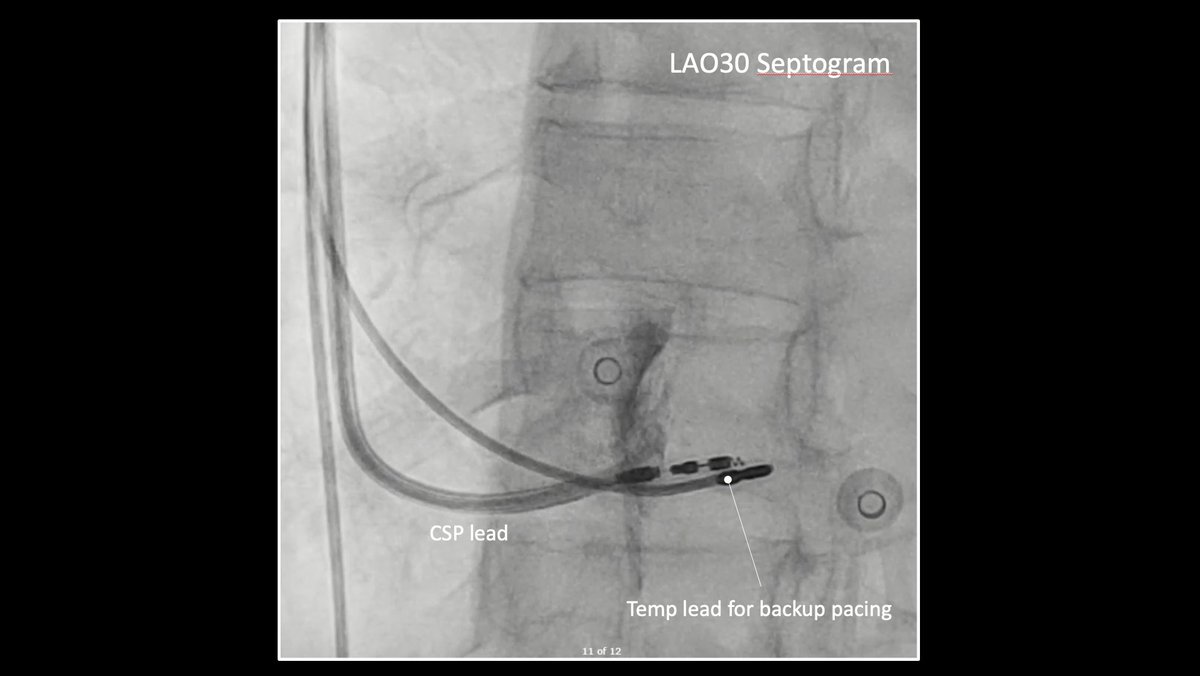

7/ Slow pathway targeted for ablation. 6s of RF was enough to totally remove the two for one responses (TFORs). Post ablation everything normalised. I thought this was a rare but satisfying case. @finnakerstrom

6/ EP study showed helped confirm. There was no VA conduction. Antegrade conduction showed continuous double fire responses without tachycardia. Very hard to systematically do an EP study.